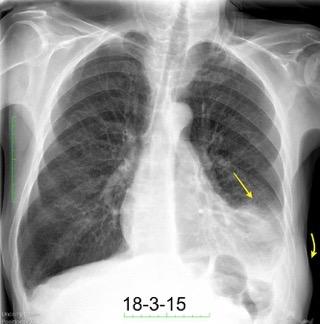

Marzo 2014: Perforación longitudinal distal secundaria a episodio de vómito (síndrome de Boerhaave). Derrame pleural izdo. que evoluciona a empiema.

Wang C-T et al. Tension hydropneumothorax in a Boerhaave syndrome patient: A case report . World J Emerg Med, 2021. Katabathina V et al. Nonvascular, nontraumatic mediastinal emergencies in adults:a comprehensive review of imaging findings. Radiographics. 2011.